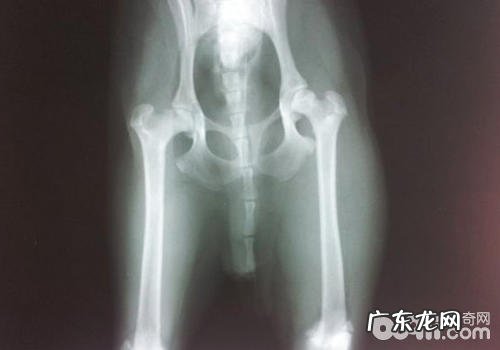

医师一般会开展腹部体格检查,很可能必须照X光,明确有木有骨裂、骨节移位等难题 。依据骨裂的比较严重水平,很有可能必须转诊证明到脑外科专业医生那边动手术 。皮下组织负伤很有可能必须应用消炎止痛药并歇息好 。

解决:一定要立即就诊 。医师会做神经系统查验,X光来鉴别受影响的脊柱部位 。如果有标准得话,脊神经造影检查,CT或MRI会出现更精确的結果 。依据病况的严重后果,医师会挑选用药治疗或是手术医治 。

5.基因遗传或是发育不全所引起

小狗如果有基因遗传或是生长发育导致的病症得话,一般出現瘸腿的年纪较为小,并且突发的概率并不大 。像犬髋关发育不良症CHD,腕关节发育不良elbow dysplasia等 。假如儿时营养成分不平衡,也会造成 人体骨骼和骨节发育不全 。